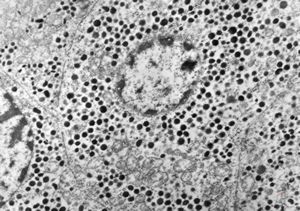

F, 72y. | carcinoid … metastasis to lymphonode